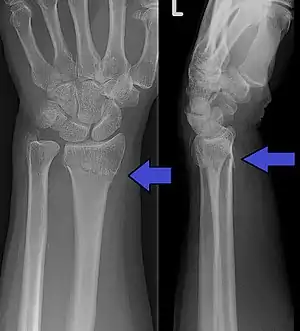

| A شکستگی کالیس as seen on X-ray. It is a type of distal radius fracture. | |

شکستگی دیستال رادیوس یکی از شایعترین شکستگیهای استخوان رادیوس است. به خاطر نزدیک بودن محل شکستگی به مچ، گاهی از آن با نام شکستگی مچ یاد میشود. درمان در موارد ساده جااندازی و بیتحرکی است اگرچه در موارد پیچیده شامل جراحی نیز میشود. بر اساس محل شکستگی و جهت جابهجایی به انواع متفاوتی شامل شکستگی کالیس، شکستگی اسمیت، شکستگی بارتون تقسیمبندی میشود.

تشخیص بالینی با بدشکلی انتهای رادیوس است که با رادیوگرافی تایید میشود. تشخیصهای افتراقی شامل شکستگی استخوان هلالی و دررفتگی مچ است که میتوانند به صورت همزمان وجود داشته باشند.